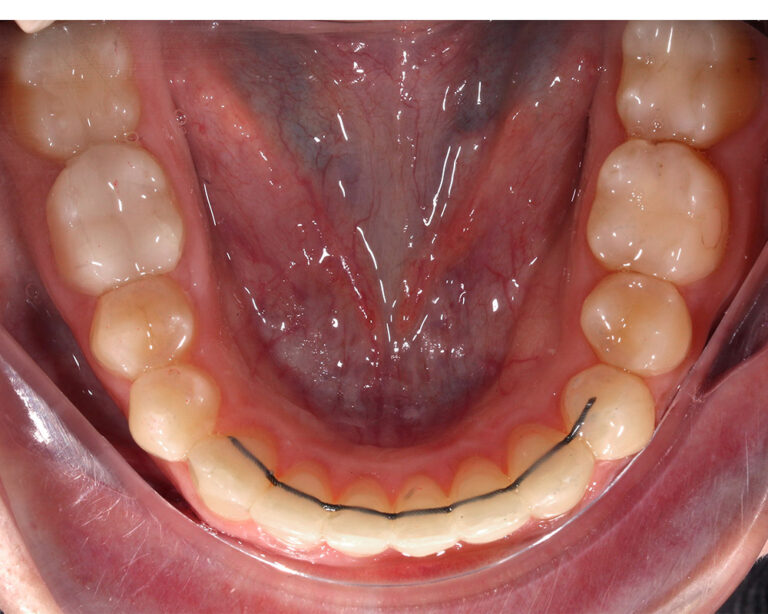

Кейс 13

Булгач (Мочалова) Галина Игоревна

Количество кап ВЧ 19

Количество кап НЧ 24

ДО

ПОСЛЕ